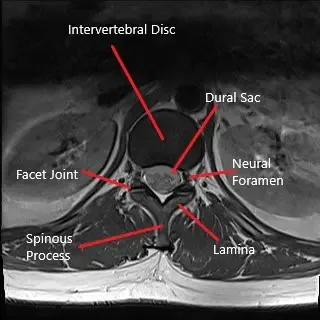

La compresión severa del saco dural puede causar el síndrome de la cauda equina. El síndrome de la cauda equina puede presentarse con debilidad en las extremidades inferiores junto con incontinencia intestinal y vesical.

La cirugía consiste en una pequeña incisión en la parte baja de la espalda y el uso de un microscopio quirúrgico para ampliar la incisión. El cirujano extrae una pequeña parte de la lámina y procede a la extracción del disco intervertebral herniado. La incisión se cierra en capas y se aplica una pequeña venda.

La microdiscectomía puede estar asociada a complicaciones tanto durante como después de la cirugía. Durante la cirugía pueden presentarse complicaciones por hemorragia excesiva, daño neural o rotura del saco dural. Puede haber complicaciones adicionales poco frecuentes en la cirugía durante el embarazo que puedan causar parto prematuro o rotura prematura de membranas. Tras la cirugía, pueden presentarse complicaciones como infección, fibrosis epidural y fallo de discectomía.